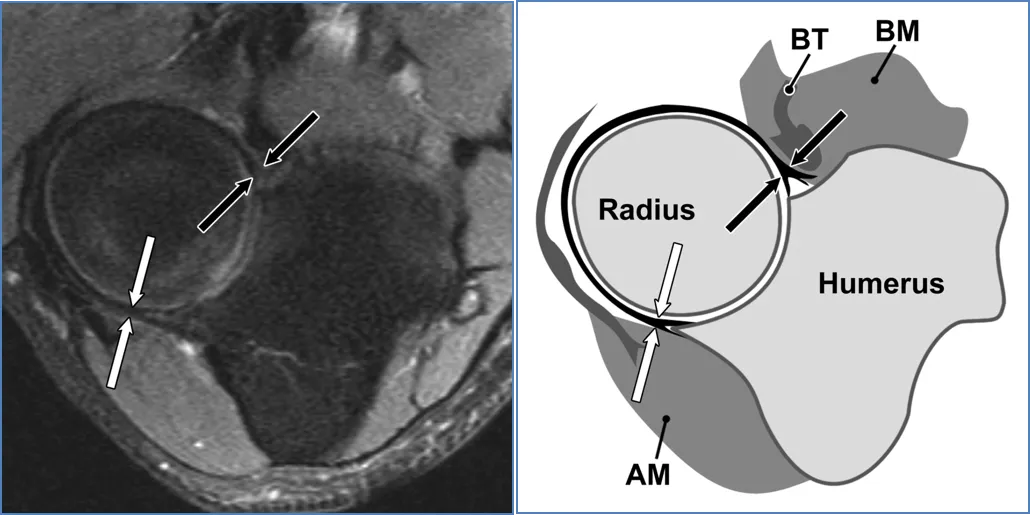

环状韧带(AL)

(a) 40岁男性横轴位中等加权脂肪抑制磁共振成像显示环状韧带与桡骨切迹的后方(白色箭头)和前方(黑色箭头)连接及其绕桡骨头的路径。(b) AL对应示意图显示AL在径向缺口上的后部(白色箭头)和前部(黑色箭头)连接。AM = 无尾肌,BM = 肱肌,BT = 肱肌腱。